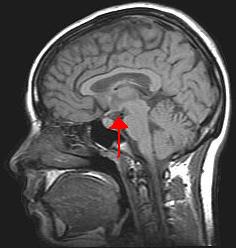

뇌 이미징은 다양한 과제를 수행하는 동안 뇌 내의 활동을 분석하는 것을 포함한다. 이를 통해 행동과 뇌 기능을 연결하여 정보 처리 방식을 이해하는 데 도움을 준다. 다양한 유형의 영상 기술은 시간적(시간 기반) 및 공간적(위치 기반) 해상도가 다르다. 뇌 이미징은 종종 인지 신경과학에서 사용된다.

- 기능적 자기 공명 영상(fMRI): fMRI는 뇌의 다른 부분으로 흐르는 산소 공급 혈액의 상대적 양을 측정한다. 특정 영역에 더 많은 산소 공급 혈액이 있다는 것은 해당 뇌 부분의 신경 활동이 증가한다는 것과 관련이 있는 것으로 가정한다. 이를 통해 뇌의 다른 영역 내에서 특정 기능을 국소화할 수 있다. fMRI는 중간 정도의 공간 및 시간 해상도를 갖는다.